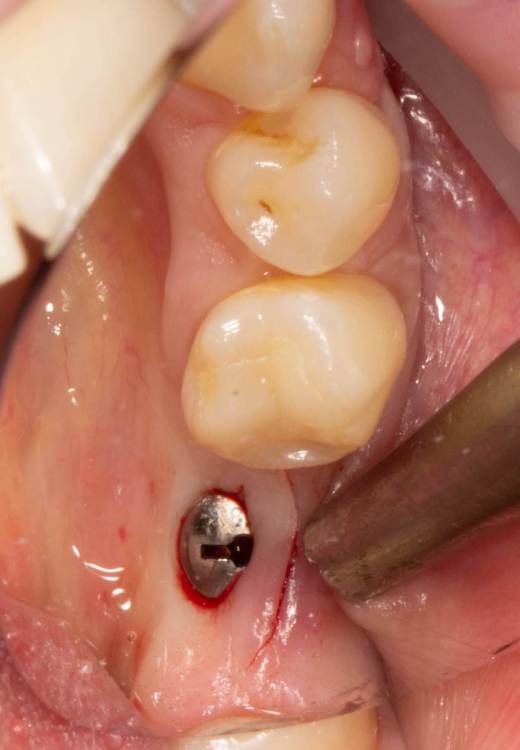

Женька Опубликовано 19 июня, 2023 Поделиться Опубликовано 19 июня, 2023 Здравствуйте, коллеги. Примерно с нового года начал ставить ТЛ имплантаты Дентиум. Что-то под заглушку (не поймал торки, представляете?). Что-то на низких формирвателях. И вот пришла пора протезирования, но отпустить к ортопеду не подготовив десну - не получается. Создал сам себе проблем, сегодня вот исправлял. Получилось неплохо? 3 Ссылка на комментарий

TIGER Опубликовано 20 июня, 2023 Поделиться Опубликовано 20 июня, 2023 Это ж не TL,cубкрестально же.А так я бы длиннее брал ССТ,с захватом соседей Ссылка на комментарий

Женька Опубликовано 20 июня, 2023 Автор Поделиться Опубликовано 20 июня, 2023 @TIGER в смысле это не ТЛ?))) Фото с редукцией не сделал. А то что, шейку погружал - так нужно было. Но это ТЛ. Поверьте) я был на имплантации) Ссылка на комментарий

АнтонТЛТ Опубликовано 20 июня, 2023 Поделиться Опубликовано 20 июня, 2023 Думаю имеется ввиду что имплантат TL установлен по протоколу BL Ссылка на комментарий

Женька Опубликовано 20 июня, 2023 Автор Поделиться Опубликовано 20 июня, 2023 @АнтонТЛТ мы же позиционируем платформу относительно зенита? Есть ли разница тогда, какой имплантат мы выбираем? Вообще весь смысл здесь был заложен в том, что толщина гребня была не очень. Хотелось поставить тонкий имплантат 3.6. Но рисковать тонкой платформой не хотелось, поэтому выбор пал на 4.8 платформу ТЛ и тело имплантата 3.6 1 Ссылка на комментарий

АнтонТЛТ Опубликовано 20 июня, 2023 Поделиться Опубликовано 20 июня, 2023 Конечно относительно зенита, не вдаваясь в подробности, для BL глубже зенита на 3мм, для TL вровень с зенитом. Ссылка на комментарий